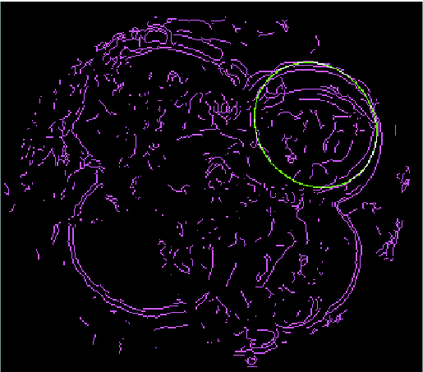

We present a novel method for identification of the boundary of embryonic cells (blastomeres) in Hoffman Modulation Contrast (HMC) microscopic images that are taken between day one to day three. Identification of boundaries of blastomeres is a challenging task, especially in the cases containing four or more cells. This is because these cells are bundled up tightly inside an embryo's membrane and any 2D image projection of such 3D embryo includes cell overlaps, occlusions, and projection ambiguities. Moreover, human embryos include fragmentation, which does not conform to any specific patterns or shape. Here we developed a model-based iterative approach, in which blastomeres are modeled as ellipses that conform to the local image features, such as edges and normals. In an iterative process, each image feature contributes only to one candidate and is removed upon being associated to a model candidate. We have tested the proposed algorithm on an image dataset comprising of 468 human embryos obtained from different sources. An overall Precision, Sensitivity and Overall Quality (OQ) of 92%, 88% and 83% are achieved.